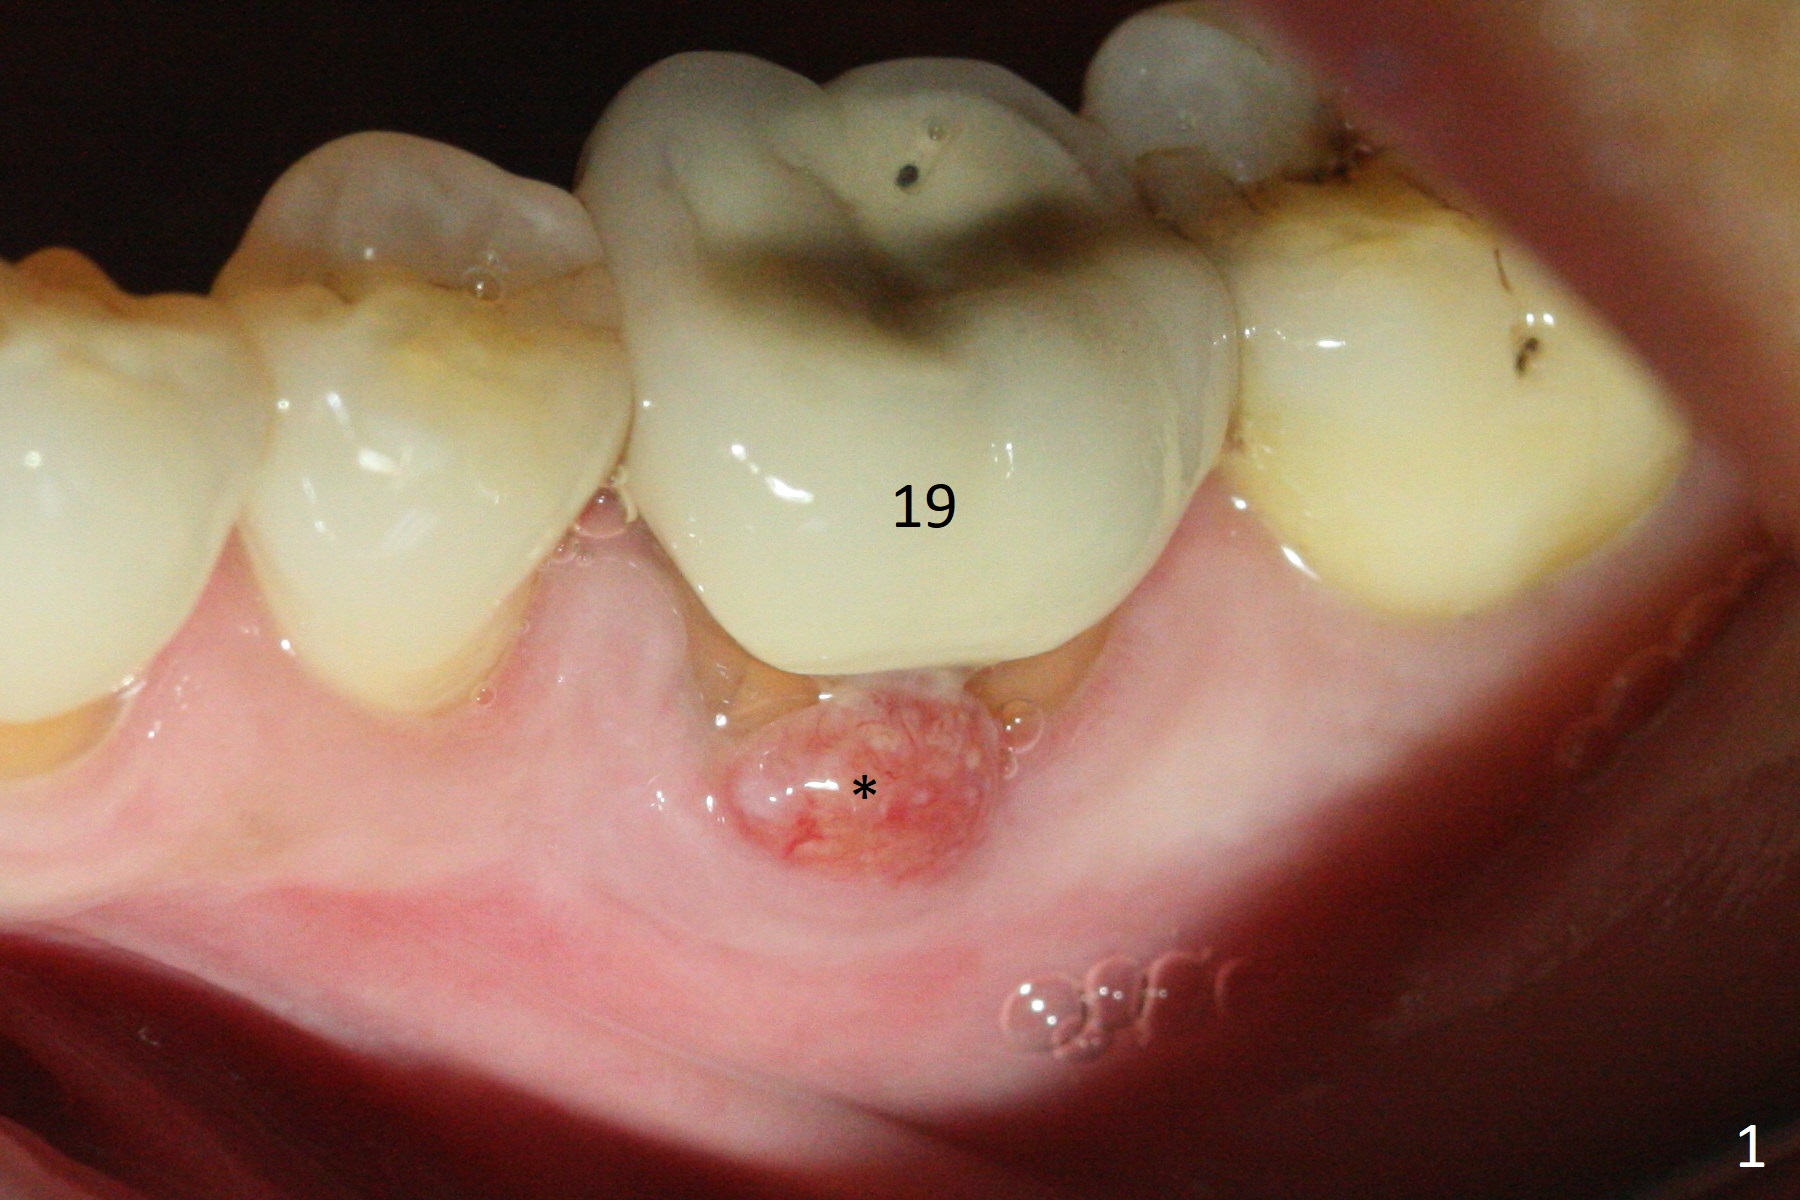

When the patient returns 9 months later, there is severe buccal gingival recession and abscess at #19 (Fig.1 *) with large mesial periradicular radiolucency (Fig.2 *).  The septum is thin and the buccal crest is low after extraction (Fig.3 * (mesial root vertical fracture)).  Osteotomy is initiated in the mesial socket immediately against the septum (Fig.4.5) with ~ 5 mm in the native bone.  Due to severe buccal plate resorption, a shorter implant is placed (Fig.6; 5x15 mm in stead of 18 mm).  There is at least 2 mm gap buccally for Vanilla Graft, which is also placed next to the implant and the neighboring root (Fig.7 *).  There is clearance from the Inferior Alveolar Canal (Fig.8 red dashed line).  Both the mesial and distal sockets heal 5.5 months postop (Fig.9), although the apical portion of the distal socket was not filled with allograft (Fig.7).  The implant was placed mesial.  The straight abutment (6.5x4(4) mm) (Fig.10) is changed to an angled one (5.5 x15 degrees 3 mm cuff (Fig.11)) before impression.  The implant is also placed buccally.  Therefore the implant position is far more important than its length.  The abutment is retightened 2.5 months post cementation, which is related to mesiobuccal placement of the implant (Fig.12).  An ideal trajectory is determined by drawing 2 horizontal lines (at crestal and apical levels: red lines in Fig.13), finding a central point of each line (vertical short line) and joining these 2 central points (Fig.14 pink line).  In fact the ideal osteotomy should have been established distal to the septum in this case.  Guided surgery may alleviate the issue.  The crown is not loose, but the patient feels that the implant tooth cannot sustain mastication.  In fact the screw is removed with hand driver (not wrench).  The abutment hex is rounded and worn.  A new 5.5x4(4) mm abutment is placed (without knowledge of previous use of an angled abutment) with mesial reduction to reduce undercut and buccodistal margin lowered to reduce gingival embrasure. It is that the straight abutment could decrease the chance of screw loosening.  Otherwise the implant has to be removed for better trajectory.